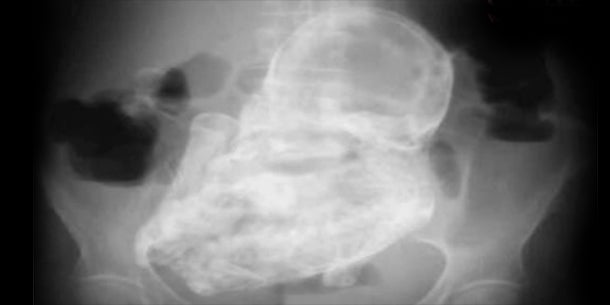

Eine skurrile Entdeckung machten Ärzte in Kolumbien: Sie haben einen 40 Jahre alten Fötus im Unterleib einer 82-jährigen Patienten entdeckt. Dieses seltene Phänomen wird in der Medizin "Steinkind" (Lithopädion) genannt, weil der abgestorbene Fötus in einem solchen Fall im Mutterleib eingekapselt wird.

Die Frau wurde mit einer Durchfallerkrankung und starken Bauchschmerzen ins Krankenhaus in die Hauptstadt Bogota gebracht. Der Fötus wurde bei einer Röntgenuntersuchung entdeckt. Um den Fötus zu entfernen, wurde die 82-Jährige in eine andere Klinik verlegt. Dort wird das "Steinkind" operativ entfernt.

Ein Steinkind entsteht, wenn der abestorbene Fötus nicht wie üblich vom Körper resorbiert wird, sondern stattdessen durch Aufnahme von Kalk eingekapselt und mumifiziert wird. Nicht immer wird die "Steinfrucht" entdeckt, oft geschieht das erst nach dem natürlichen Tod der Mutter. Das Phänomen "Steinkind" ist sehr selten. Bisher wurden weniger als 300 Fälle dokumentiert.